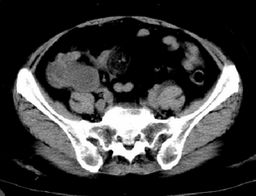

标题: CT9081:仍然是右下腹占位,仍于明天公布结果

右侧下腹疼痛,二便常规正常,其他化验室检查无异常

1.脓肿应该周围脂肪层有所反应;2.该病变外侧缘光滑、但内侧缘毛糙界限不锐利,其下壁密度较高。可仔细观察下面两幅图像

考虑阑尾炎并周围脓肿形成还是不充分的,请仔细观察9075和9081的图像吧。

ct9075:病变张力较大、边缘光滑、内壁光滑。

ct9081:病变分叶、外缘虽光滑但内壁毛糙可见结节。

9081结果公布:腺样囊性癌。

学习了,炎症性病变,似病变与周边渗出不相称.与临床不太相符合.腺样囊性癌.兰尾来源的吗?

腺样囊性癌,还是发生于阑尾的吧。诊断粘液囊肿也不算误诊。

粘液囊肿是由于阑尾腔的闭塞,造成粘液的异常积聚,导致阑尾腔的扩大而形成的囊性肿块。阑尾的粘液囊肿可分为三种类型:1.单纯潴留囊肿。2.粘液囊腺瘤。3.粘液囊腺癌。